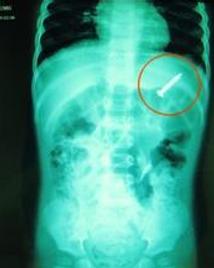

胃内异物(foreign body in stomach)分为外源性、内源性以及在胃内形成的异物即胃石症。吞入的异物中有20%~30%在食管内受阻而滞留。80%以上的胃内异物可自行排出胃腔,自肠道从大便中排出体外,很少引起不适或只有轻微的上腹部隐痛、胀满、恶心等症状。